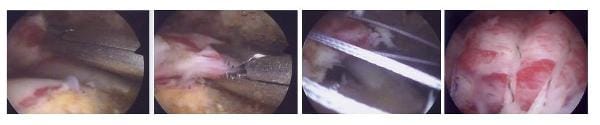

ARTHROSKOPISCHE SEHNENNAHT

Bild Spiegelung die Sehne wird mit einer Fasszange gegriffen mit Fäden versehen und wieder am Knochen mit Ankerschrauben befestigt

Beispiel einer arthroskopischen Sehnennaht: Die Sehne wird mit einer Fasszange gegriffen, mit Fäden versehen und wieder am Knochen mit Ankerschrauben befestigt. (Bilder: Orthopädie)